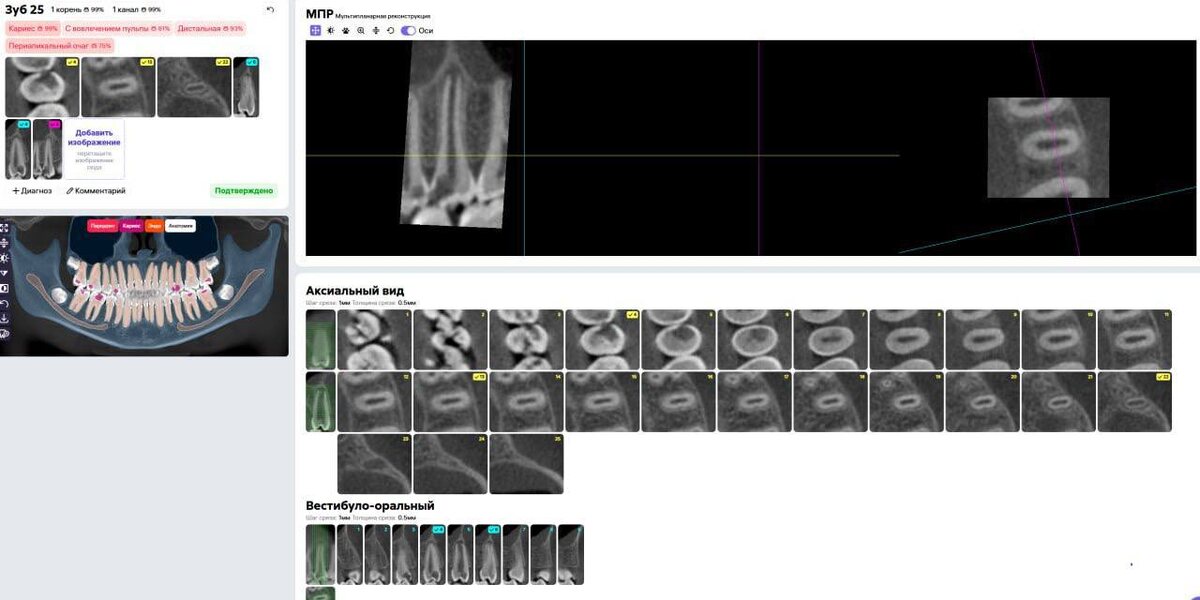

В каких случаях мы не можем выбрать тактику применения витальной терапии пульпы с разбором моего кейса. Этот разбор – пример того, как системный подход и понимание биологии тканей помогают принимать обоснованные клинические решения. 👉 Для коллег, которые хотят углубить и выстроить свою клиническую практику, разобраться в тактике лечения несформированных постоянных зубов и уверенно выбирать протоколы в сложных случаях, я рекомендую серию вебинаров, приобрести можно мой бот-помощник @GuzunENDO_bot